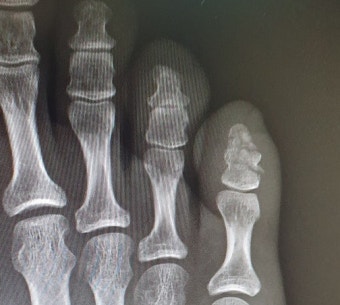

병원에 가면 대부분 X-ray(엑스레이) 촬영을 합니다. 간단하고 빠르게 뼈 상태를 확인할 수 있어요. 경우에 따라 미세 골절이 의심되면 추가 검사가 필요할 수도 있지만, 대부분은 X-ray로 충분합니다.